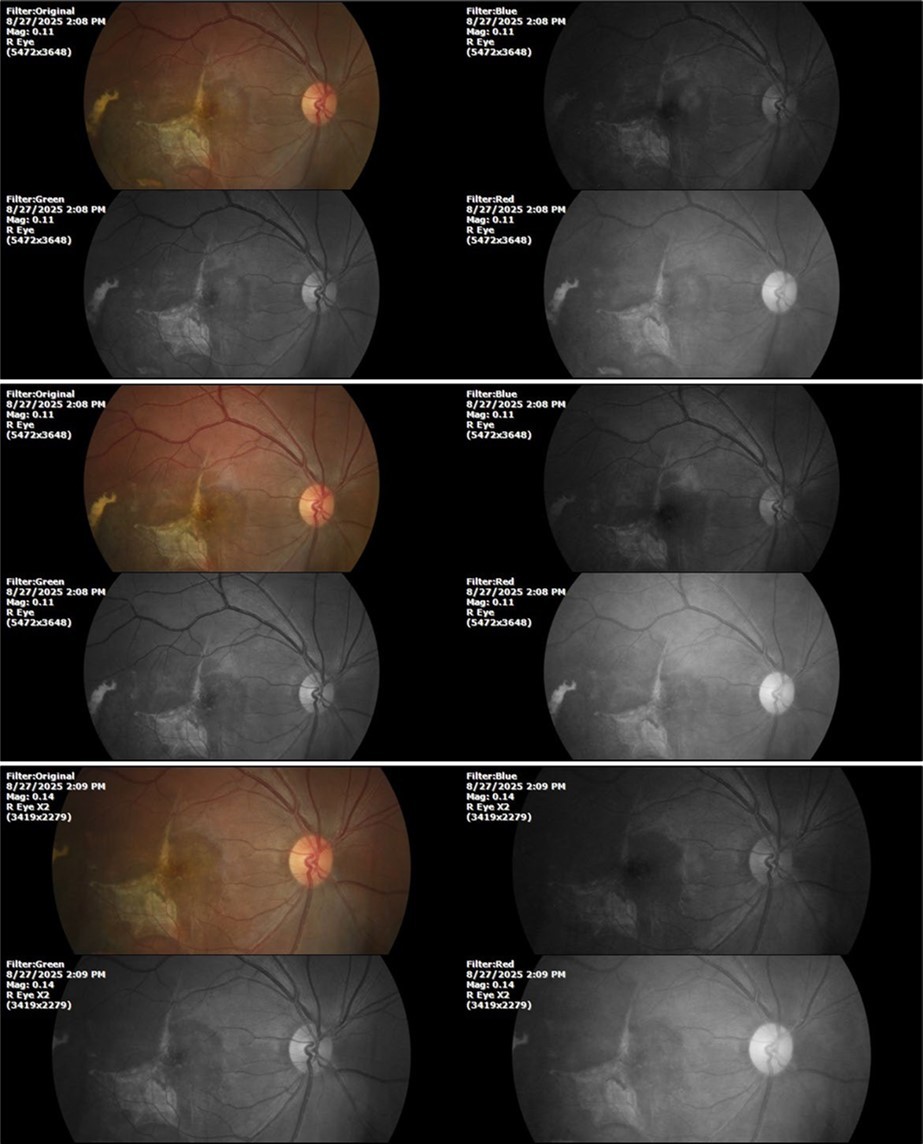

Figure 31.The photograph of the right eye shows an almost normal mirror reflection, as well as a better pupillary dilation.

The photograph of the right eye shows an almost normal mirror reflection, as well as a better pupillary dilation.

Figure 32.The macro photograph of the right eye shows us a cornea, anterior camera, and crystalline lens in very good condition.

The macro photograph of the right eye shows us a cornea, anterior camera, and crystalline lens in very good condition.

Figure 33.The 3 previous photographs show that whitish mass has almost completely disappeared, and to date only a remnant remains on the left side of the photograph. The chorioretinal scar that is now observed corresponds to the area affected by the blunt trauma, which presumably caused rupture of Bruch's membrane. Fortunately, the macular region has recovered almost in its entirety, so the impairment in central vision was minimal.

The 3 previous photographs show that whitish mass has almost completely disappeared, and to date only a remnant remains on the left side of the photograph. The chorioretinal scar that is now                  observed corresponds to the area affected by the blunt trauma, which presumably caused rupture of Bruch's membrane. Fortunately, the macular region has recovered almost in its entirety, so the impairment in central vision was minimal.